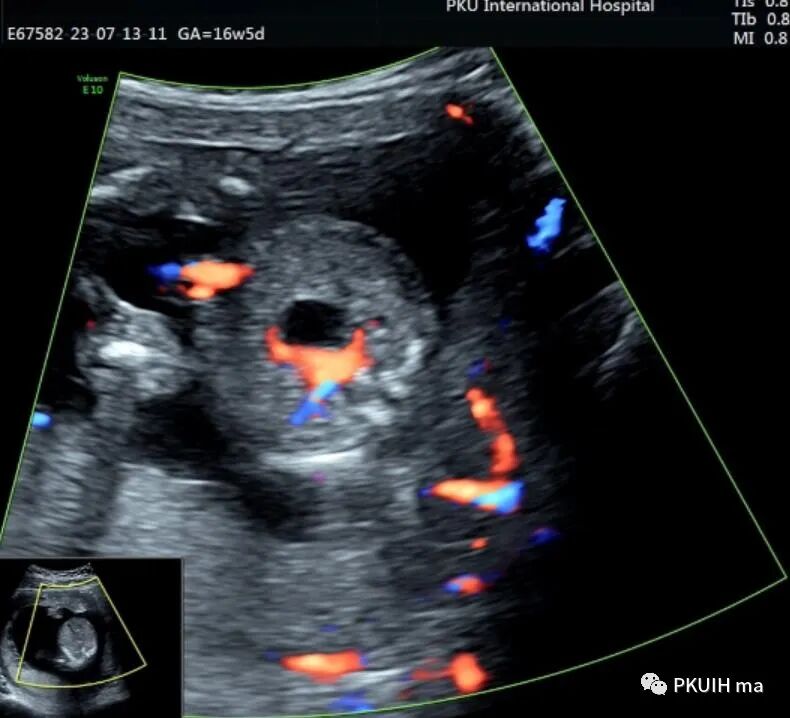

胎儿中腹部见一囊性包块,大小约1.2x1.0x0.8cm,边界清,形态规则,内透声好。囊肿位于脊柱前方、胆囊后方、门静脉窦旁,与后肾接近

观察囊肿与肾、胃泡、膀胱均无相关。

仔细观察囊肿壁好像不完整,周边见微小管道回声与囊肿相通

CDFI:囊肿内未见明显血流信号。

由于囊肿位于胆囊后方、肝下方、门静脉窦旁,随考虑为胆总管囊肿

本病可于中孕及晚孕期被发现,其超声特征为肝门区囊性包块,形状呈圆形或椭圆形,位于门静脉右前方,可对门脉造成压迫。如果显示囊性包块与胆囊相通,则有助于诊断,彩超一般内部无血流信号。